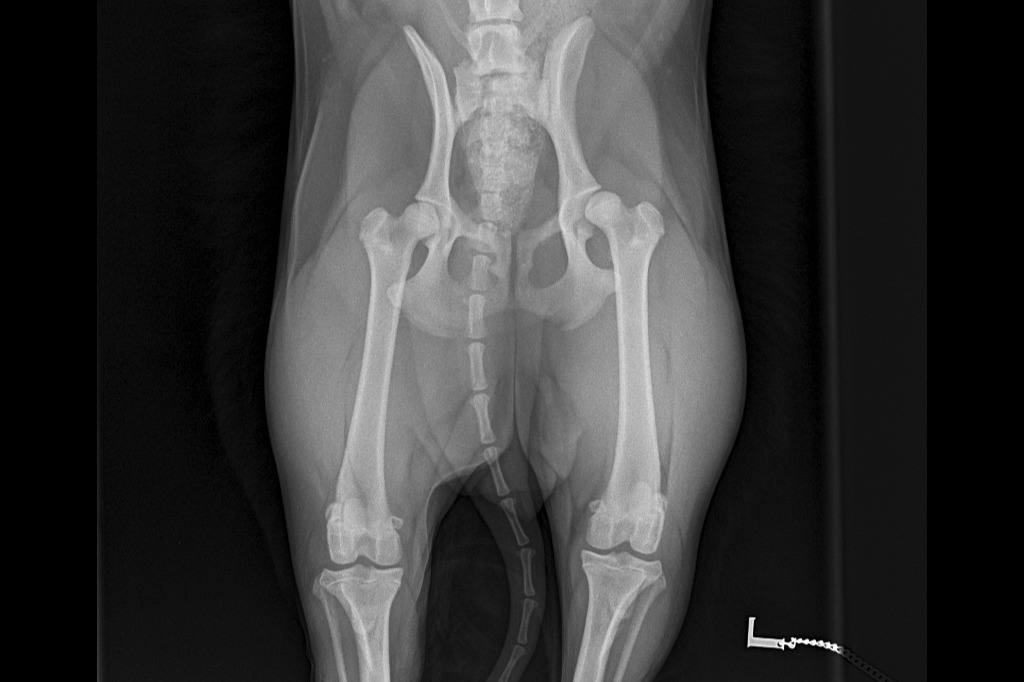

I can't walk anymore and the Vets said I have Luxating Patella issues and I need a surgery. I am scared to wee/poo because my legs would hurt if I flex/squat to wee/poo. My pictures below are the recent pictures after this incident and before the incident. If you want to see more pictures of me being lively and happy, please check my Instagram Profile lupe_gordita.